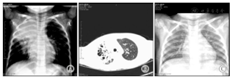

4例X线检查均示肺实质病变。例1,病程11 d CT示右上肺片状高密度影,病程20 d CT示双肺多个大小不等囊状影,右上肺显著。见图1A、图1B;3个月后复查胸片肺炎基本吸收,见图1C。例2,病程15 d肺CT:左侧胸廓略塌陷,左肺上叶大片状密实影,内见液平囊状影,见图2A、图2B;18个月后复查肺CT示左上肺脓肿消失,留有部分肺不张、条索影,见图2C。例3,病程6 d胸片示右上肺大片状高密度影,病程17 d肺CT示右上中肺大片及点状高密度影,右下肺背段多个厚壁空洞,呈簇状沿支气管分布,纵隔淋巴结大,见图3A、图3B。3个月后复查胸片肺炎基本吸收,见图3C。例4,病程5 d胸片示左上肺组织坏死,见图4A。0.5年后复查胸片提示炎症较前明显吸收,见图4B。

注:A:2010-03-31胸片示右上肺大片状密度增高影;B:2010-04-12肺CT示右下肺背段多个厚壁空洞;C:2010-06-21胸片示右侧肺炎症基本吸收